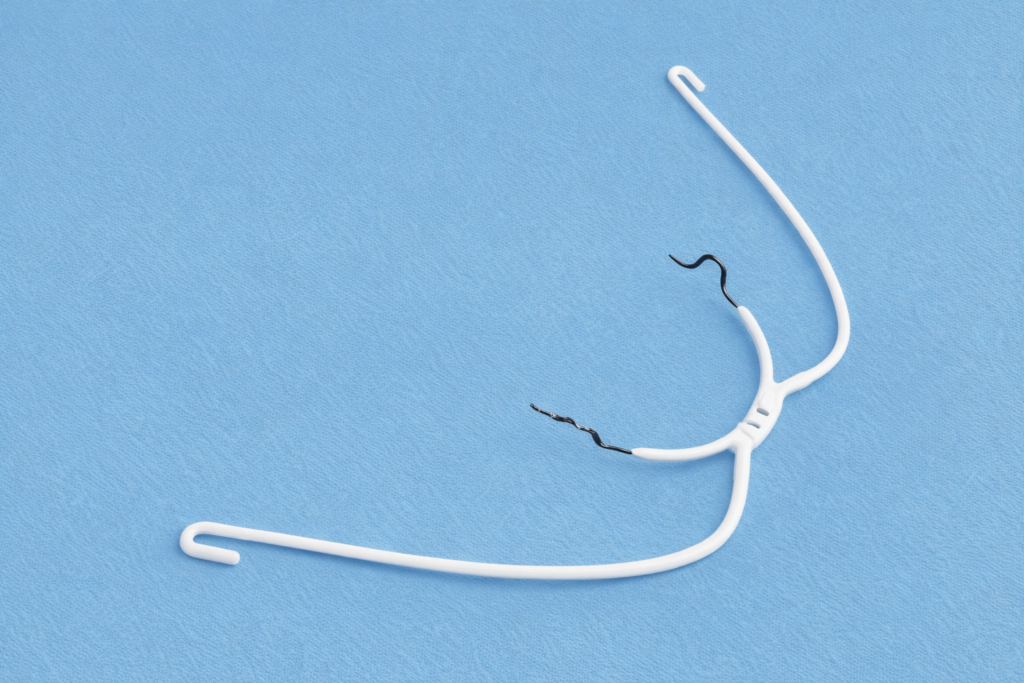

午前-102

矯正歯科治療用器具の写真を別に示す。 適切な用途はどれか。1つ選べ。

a.アーチワイヤーの屈曲

b.マルチブラケットの位置決め

c.歯冠近遠心径と歯列弓長径の計測

d.バンドへのアタッチメント点溶接

解答を見る

a